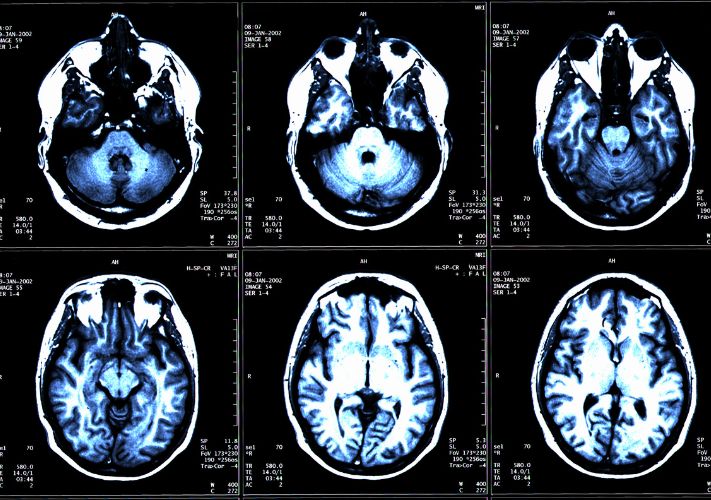

Diagnostic tests are medical tests that are performed to help diagnose a disease, condition, or injury. There are many different types of diagnostic tests, and the specific tests used will depend on the patient's symptoms, medical history, and the suspected underlying cause of their symptoms. These tests use various imaging technologies to produce images of the inside of the body, including X-rays, CT scans, MRI scans, and ultrasound scans.